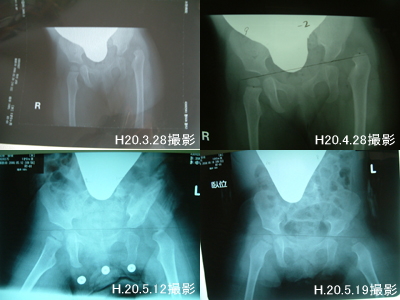

入院生活 H20.4.28 ~ H20.6.8 (42日間)

第一段階(足に包帯を巻いての水平牽引)3日間

第一段階(鋼線牽引に切り替えてから水平牽引)25日間

第二段階(開排牽引)7日間

第三段階(開排牽引)3日間

第四段階(ギプス固定)2ヶ月(予定)

(ギプス固定後4日目に退院しました)

第五段階(装具)4ヶ月(予定)

その後経過観察

【 左:整復前 右:整復後(ギブス内) 】